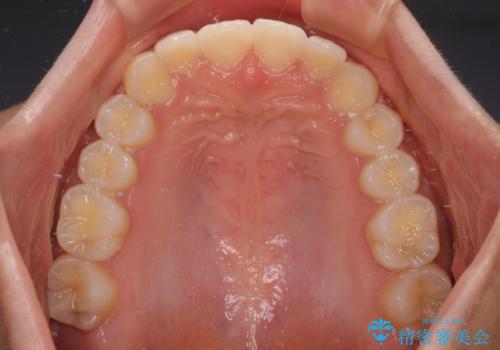

前歯のデコボコを治したい インビザライン・モデレートによる矯正治療

- 上下前歯の叢生を気にして来院された患者様です。

インビザラインでの治療を希望されていて、デコボコの程度が中等度であり、安価なパッケージにて対応可能と判断されたため、インビザライン・モデレートを用いて矯正治療を行うこととしました。

インビザライン・モデレートは、製作できるアライナーの枚数に制限があるため、移動可能な量に限りがあるものの、インビザライン・ライトよりも枚数が多いため、幅広い症例に対応可能です。